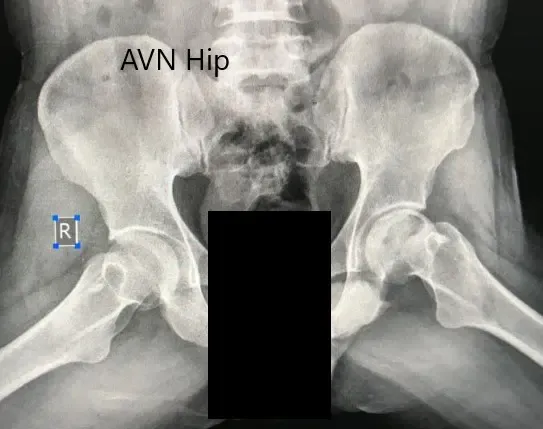

Se realizó un análisis de sangre rutinario para estimar los niveles de vitamina D sérica y electrolitos. Los estudios de imagen en forma de radiografías revelaron un aumento de la esclerosis de la cadera izquierda. Había una pequeña radioopacidad justo debajo de la superficie superior de la cabeza del fémur. Hubo cambios moderados en el acetábulo.

Radiografía preoperatoria de la pelvis con ambas caderas en vista anteroposterior que muestra el AVN de la cadera izquierda.